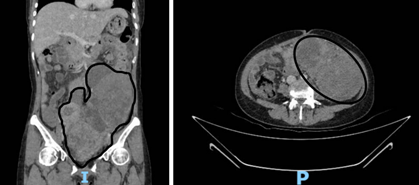

Đến năm 2024, bệnh nhân nhận thấy bụng to dần nên nhập viện tại Bệnh viện Ung Bướu TP. Cần Thơ. Kết quả CT scan ghi nhận: khối tổn thương đậm độ mô mềm kích thước khoảng 150 x 102 mm và 81 x 52 mm, kèm dịch ổ bụng và thâm nhiễm mỡ mạc treo, gợi ý nhiều đến u ác tính buồng trứng di căn ổ bụng.

Hình 1. Hình ảnh khối u trên CTscan bụng theo các mặt cắt đứng dọc và ngang ghi nhận khối u ổ bụng rất to, giới hạn không rõ với các cơ quan khác